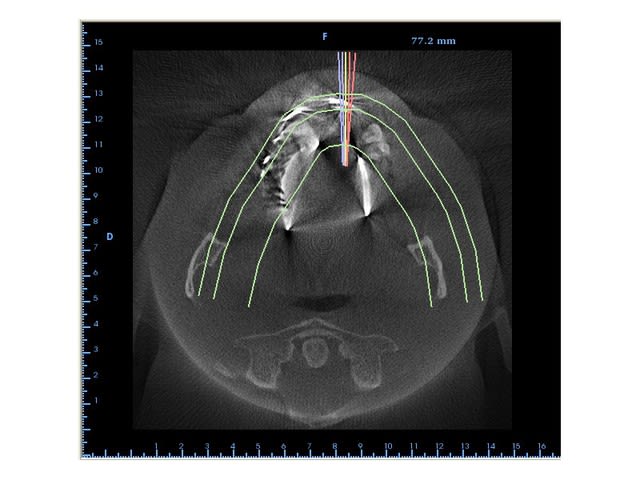

Cas prévu pour demain avec Blue Sky Plan:

2 implants Kontact (pour 2 piliers Locator par la suite) afin de stabiliser un appareil complet du bas.

L'aspect bizarre au maxillaire, c'est ...l'appareil en stellite laissé en bouche: bonjour le stroboscope disco sur la tomo...